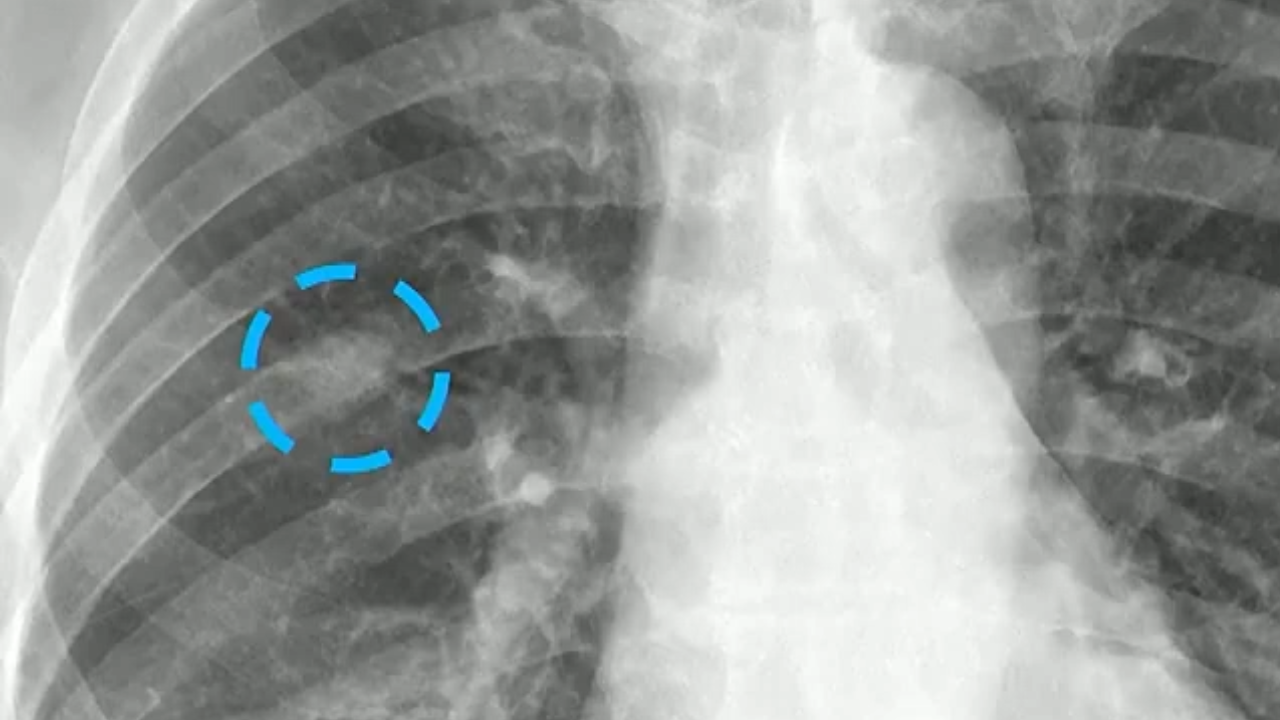

- Pericardial Effusion: The presence of a moderate-to-large pericardial effusion is a strong predictor of mortality, even when adjusting for the Society of Thoracic Surgeons clinical risk score.